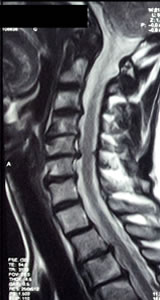

• Resonancia Magnética de la columna vertebral es el mejor método de imágenes de la médula espinal y las raices nerviosas, los discos intervertebrales y los ligamentos.